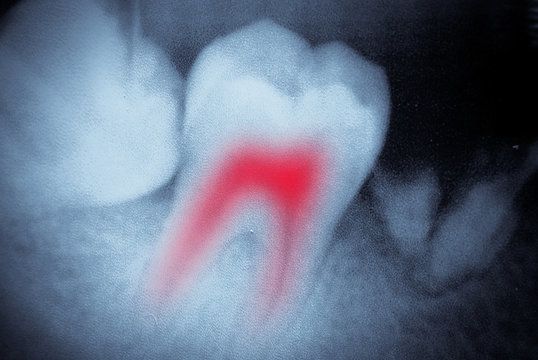

Terapia de Tratamiento de Conducto

Si las bacterias orales ha avanzado a las cámaras interiores de sus dientes, la Dra. Moncada puede utilizar la terapia de conducto radicular para aliviar el malestar y el tratamiento de la infección en su origen. Durante un procedimiento de conducto radicular, la Dra. Moncada eliminará el tejido infectado desde el interior de su diente, limpiara la zona, y llenara el espacio resultante con un compuesto similar a una goma blanda. A continuación, se remodelara el diente y se cubrira con una corona dental para restaurar su función dental y proporcionar una mayor protección contra las caries.

En Windermere Dental, nosotros orgullosamente destacamos nuestra tecnología avanzada para realizar diagnósticos precisos y proporcionar a nuestros pacientes con el más alto nivel de cuidado oral. Con los rayos X digitales, podemos capturar imágenes detalladas de los dientes y las estructuras orales, que nos permite crear un plan de tratamiento verdaderamente personalizado.